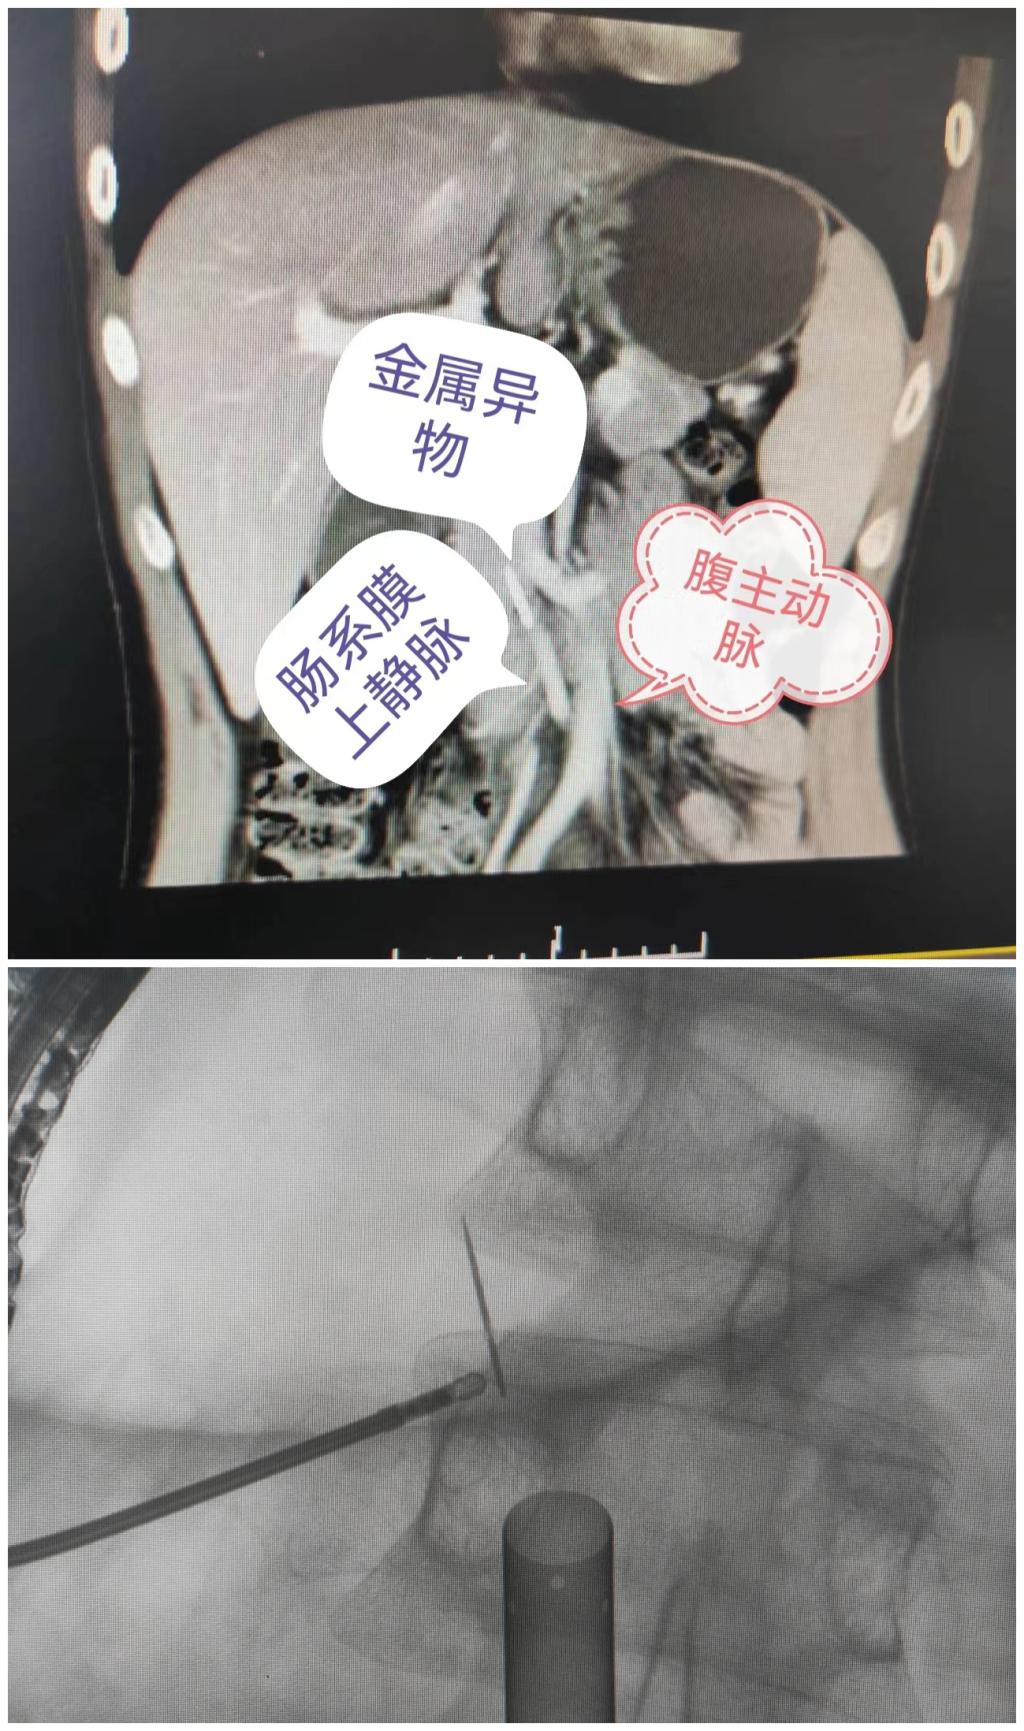

患者入院后得到院领导及科室领导的高度重视,完善相关检查后,科主任孙宏伟,副主任王东君带领科室骨干人员先进行病案讨论,发现主要异物位于胰腺钩突处,异物位于肠系膜上静脉之下,下腔静脉左侧,腹主动脉右侧,推测应该是吞食后卡到十二指肠降部和水平部交界处,由此处穿出并进入胰腺,此部位解剖结构复杂重要血管较多也是4年来未能将其取出的主要原因。然后反复再读CT片发现异物部分仍可能在十二指肠内,因此我科医疗团队制定出三套手术方案:1.通过十二指肠镜取出异物;2.通过腹腔镜取出异物;3.开腹取出异物。

术前经充分准备,2022年6月30日在我院麻醉手术室的全力保障下进行腹腔异物取出术。由王东君副主任医师担任主刀医生,助手为刘海军主治医师 、耿攀飞住院医师。先行十二指肠镜探查到达十二指肠,发现异物部分位于十二指肠内,与术前判断一致,用取物钳夹住后向外拉取,出现异物断裂,考虑异物存留体内时间过长,导致腐蚀生锈所致,遂采用第2套方案,行腹腔镜下取异物。进入腹腔、见腹腔内粘连严重、分离粘连后再在“大C”的引导下,从横结肠系膜根部入路找到肠系膜上静脉,小心解剖,将肠系膜上静脉拉向一旁,充分显露出钩突,用超声刀小心分离胰腺钩突组织,寻找到异物尖部,用持针器将其夹住,向外牵拉。因时间较久,异物与周围胰腺组织呈瘢痕样粘连、异常紧密,这也是异物断裂的原因之一,王东君副主任沉着冷静用超声刀小心翼翼将异物与周围组织分离,最后顺利安全取出,术后创面放置引流管一根,手术顺利结束。患者已于14日康复出院。